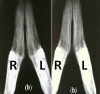

Fig. 4

Radiographic observation on day of injury. a) Left R: the defect filled with fibrin glue; Left L: the control defect, b) Right R: the defect filled with fibrin glue; Right L: the defect filled with autologous bone graft after 4 weeks.